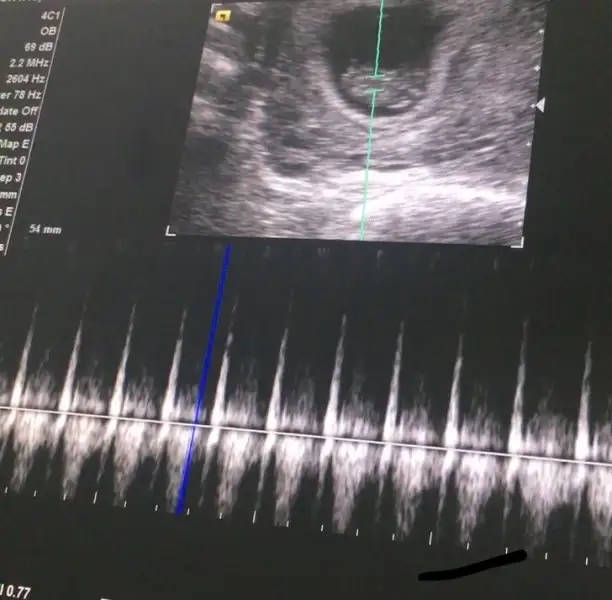

Doktor,detayli tahlil, mide bulantısı derken biraz zaman geçti ve 9.hafta içindeyim..